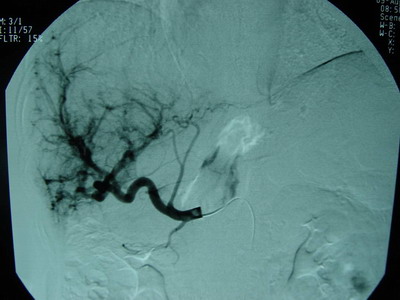

肝动脉、肠系膜上动脉、脾动脉造影见肝总动脉明显增粗,动脉期肝动脉及其分支显影良好,动脉早期可见门静脉显影,呈明显肝动脉—门静脉双轨征。肝实质期未见肿瘤染色。肠系膜上动脉间接门静脉显影,门静脉主干显影。门静脉血流方向为双向。可见胃底曲张血管逆行显影。